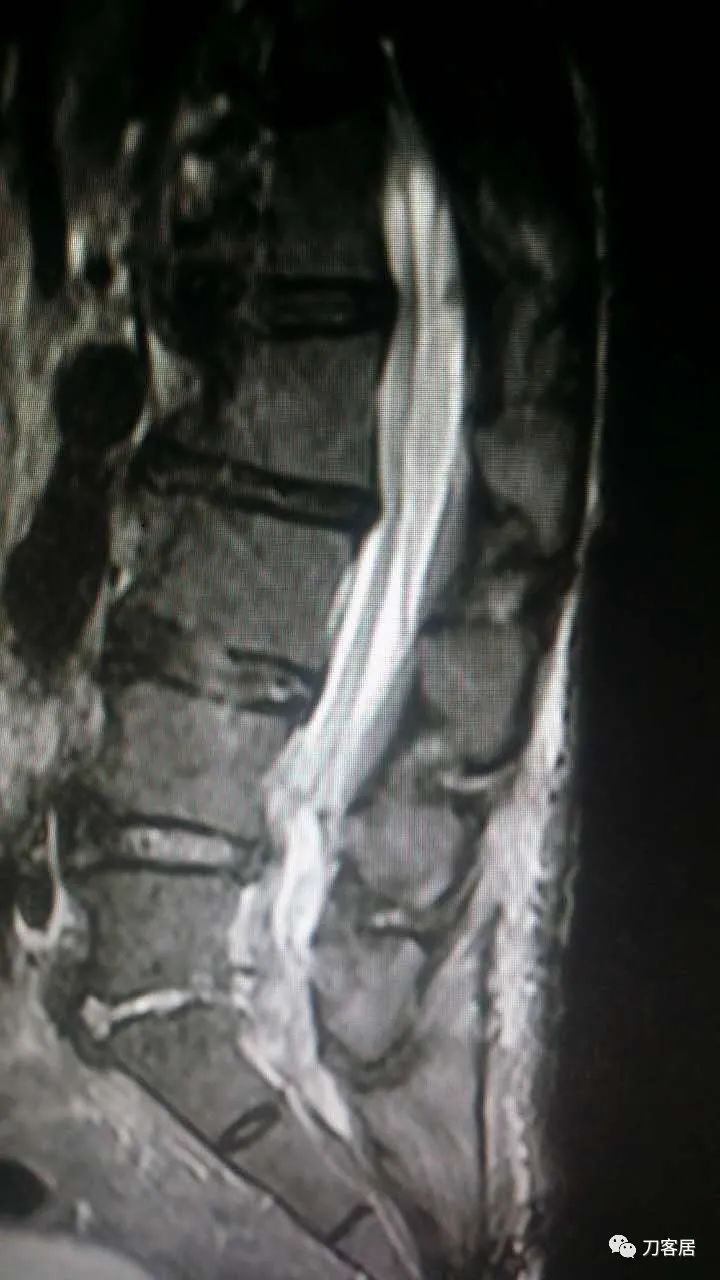

加注图10: 腰1-2椎管内后方可见梭形占位信号改变。

加注图11. 腰1-2椎管内后方可见梭形占位信号改变。

加注图14. 胸9-10椎管内后方高信号占位病变,考虑血肿形成。

加注图15. 胸9-10椎管内后方高信号占位病变,考虑血肿形成。

加注图16. 胸9-10椎管内后方高信号占位病变,考虑血肿形成。

加注图17. 胸9-10椎管内后方高信号占位病变,考虑血肿形成。

加注图21. MRI显示胸9-10和腰1-2椎管内后方占位病变,考虑血肿形成。

加注图22. MRI显示胸9-10和腰1-2椎管内后方占位病变,考虑血肿形成。